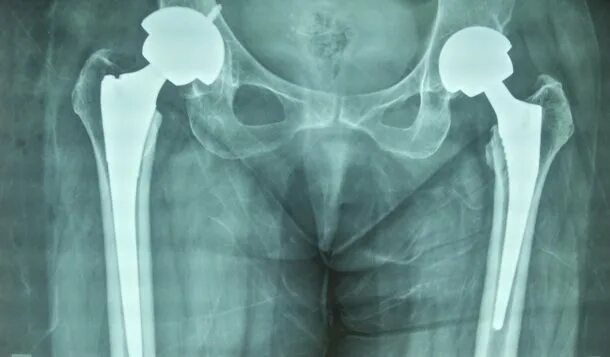

Протезирование тазобедренного сустава видео